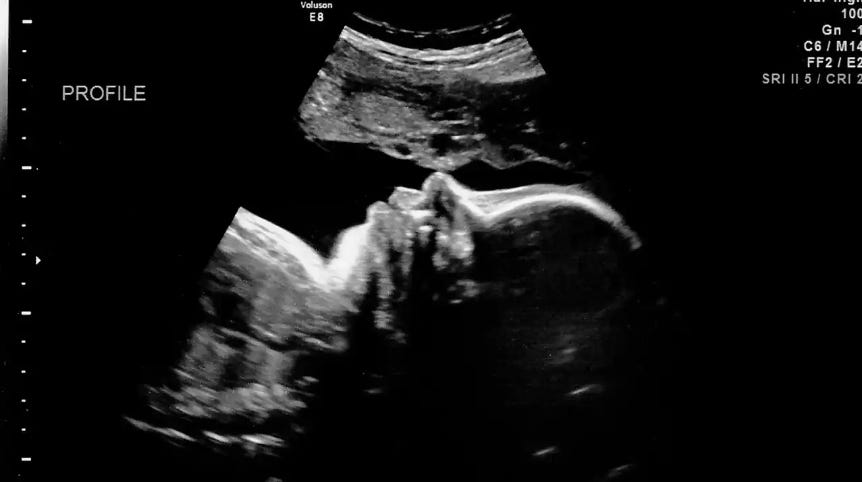

7. All that being said, it is always wrong to directly and intentionally kill innocent human life. Abortion always directly and intentionally kills innocent human life. Therefore, abortion is always wrong. Christians must hold the line on what is patently and observably true. There now exists a broad scientific consensus that life begins at fertilization. In one study out of the University of Chicago, 96% of doctors (5,337 out of 5,577 in the study) regardless of their political views, affirmed the view that life begins at fertilization (Steven Andrew Jacobs, pubmed). Complex medical conditions such as ectopic pregnancies or uterine cancer where the life of the mother is in danger and she must be treated in a way that could harm the baby is not the same as the direct and intentional killing of an innocent human life. The death of the baby may be an unintentional result of said treatments, but that is different from an abortion. In other words, women do not go to abortion clinics to treat ectopic pregnancies. The purpose of an abortion is to end the life of the baby. That is why they call a “successful” abortion one that ends with a dead baby, and a “failed” abortion one where the baby survives the procedure intended to end its life. The purpose and intent of an abortion is always to end the life of the baby in the womb and is not the same as other complex medical cases like those mentioned above.